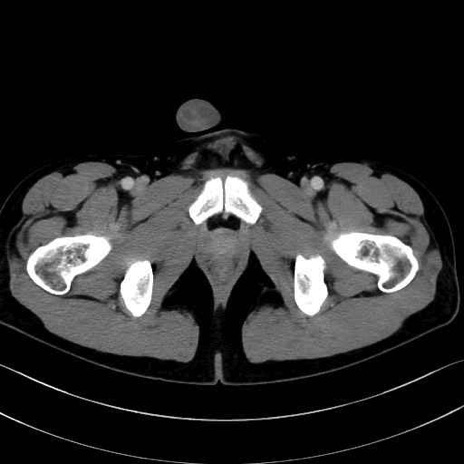

大内転筋・小内転筋 (Adductor magnus / Adductor minimus)